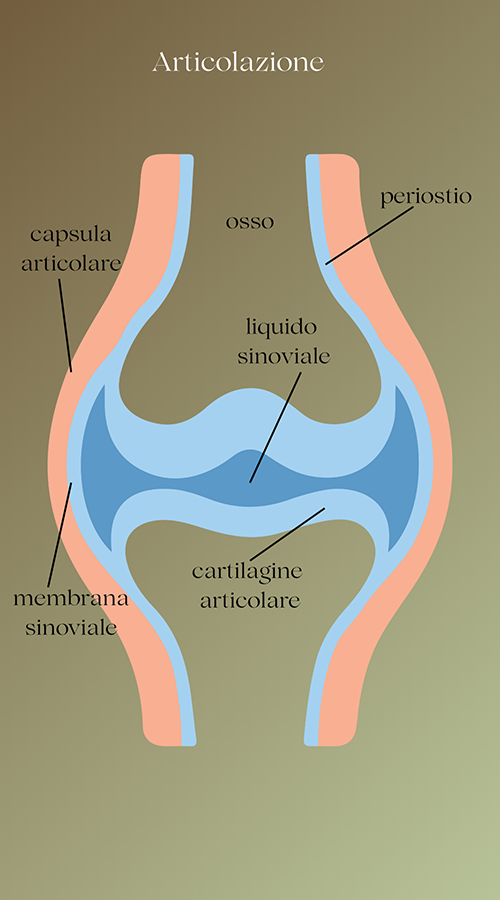

Nelle articolazioni convergono due capi ossei contrapposti, rivestiti di cartilagine e contenuti dalla capsula articolare, lubrificati dal liquido sinoviale e congiunti dai legamenti muscolari. Si tratta di zone fortemente vascolarizzate e ricche di terminazioni nervose.

Nelle articolazioni convergono due capi ossei contrapposti, rivestiti di cartilagine e contenuti dalla capsula articolare, lubrificati dal liquido sinoviale e congiunti dai legamenti muscolari. Si tratta di zone fortemente vascolarizzate e ricche di terminazioni nervose e questo non fa che amplificare il sintomo principale, cioè il dolore. L’intensità di tale sintomo muta, inoltre, in base allo stadio cui è arrivata la malattia.